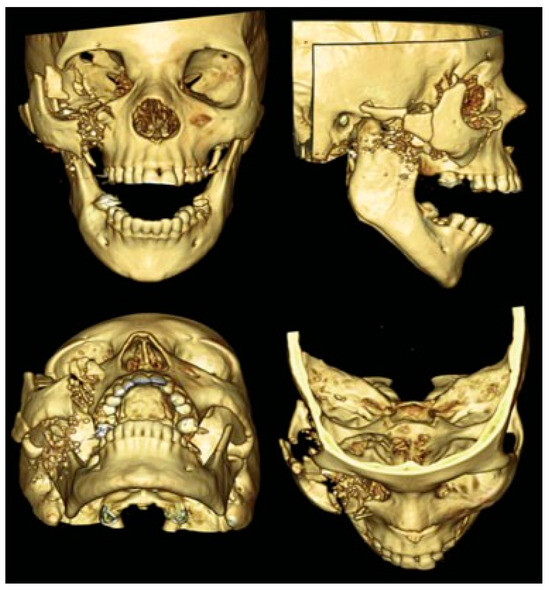

Immediate Reconstruction of Large Full-Thickness Segmental Anterior Maxillary Defect with Bone Transport

by Alberto Rocha Pereira, Nuno Montezuma, Luis Oliveira, Miguel Magalhães and José Rosa

Craniomaxillofac. Trauma Reconstr. 2016, 9(4), 305-312; https://doi.org/10.1055/s-0036-1592094 - 15 Sep 2016

Cited by 5

Abstract

Maxillary segmental defects are a reconstructive challenge particularly when the anterior arch is involved. Missing bone, mucosa, and teeth should be replaced; fistulae closure should be guaranteed by bone and mucosa continuity; stable functional occlusion should be achieved; and facial aesthetics restored. These [...] Read more.

Maxillary segmental defects are a reconstructive challenge particularly when the anterior arch is involved. Missing bone, mucosa, and teeth should be replaced; fistulae closure should be guaranteed by bone and mucosa continuity; stable functional occlusion should be achieved; and facial aesthetics restored. These defects resulting from tumor excisions, if left untreated, will cause additional problems related to interposed scar and collapse of lip and nose. Immediate reconstruction should avoid these problems and should be considered when safe tumor-free margins are obtained. This study describes the treatment of such a defect resulting from a myxoma excision, with trifocal distraction requiring only one additional surgery. Internal distractors were fixed bilaterally for transport of two segmental discs created by inverted L osteotomies at the same surgical time of tumor excision. A second surgery was performed after central contact between transport discs was achieved, for device removal and creation of a dynamic system to regenerate molding and compression-focus development. This was accomplished by internal fixation of one side and central fixation of a full-open distractor to act as compression device when reversely activated. Central perfect adaptation between transported segments and good-quality attached mucosa lining the alveolar crest were determinant to obtain a stable functional and aesthetic result. Full article

Show Figures

Figure 1